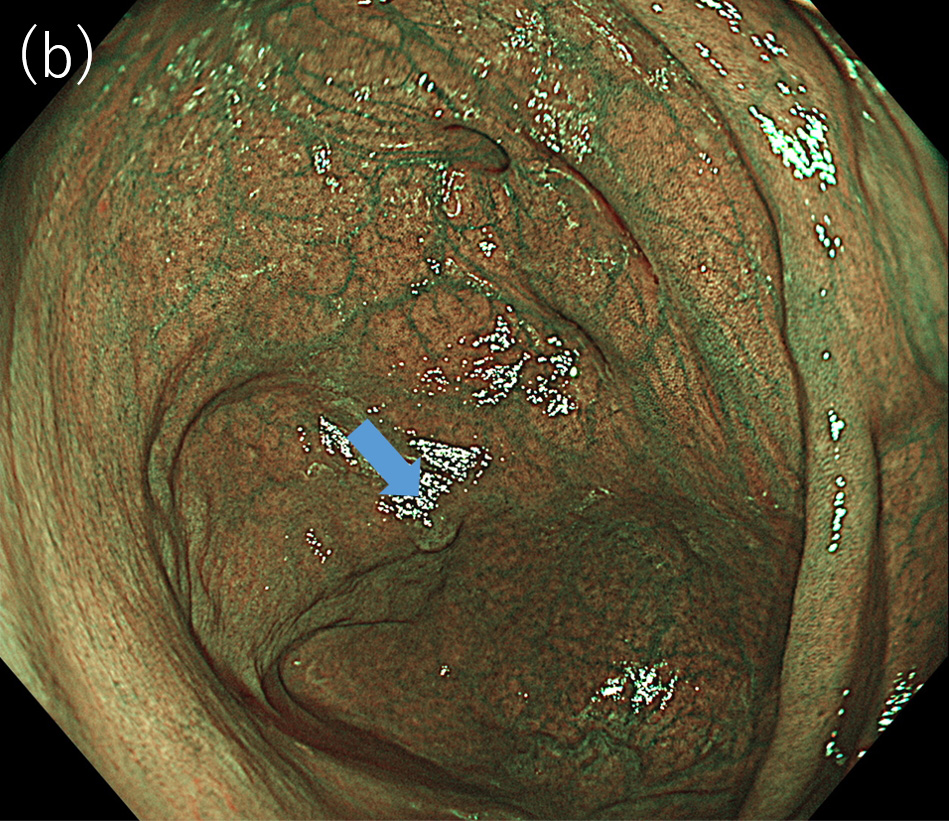

〈図2〉 XZ1200による同一病変に対するNBI中遠景観察像(a)BAI-MAC OFF; (b)BAI-MAC ON